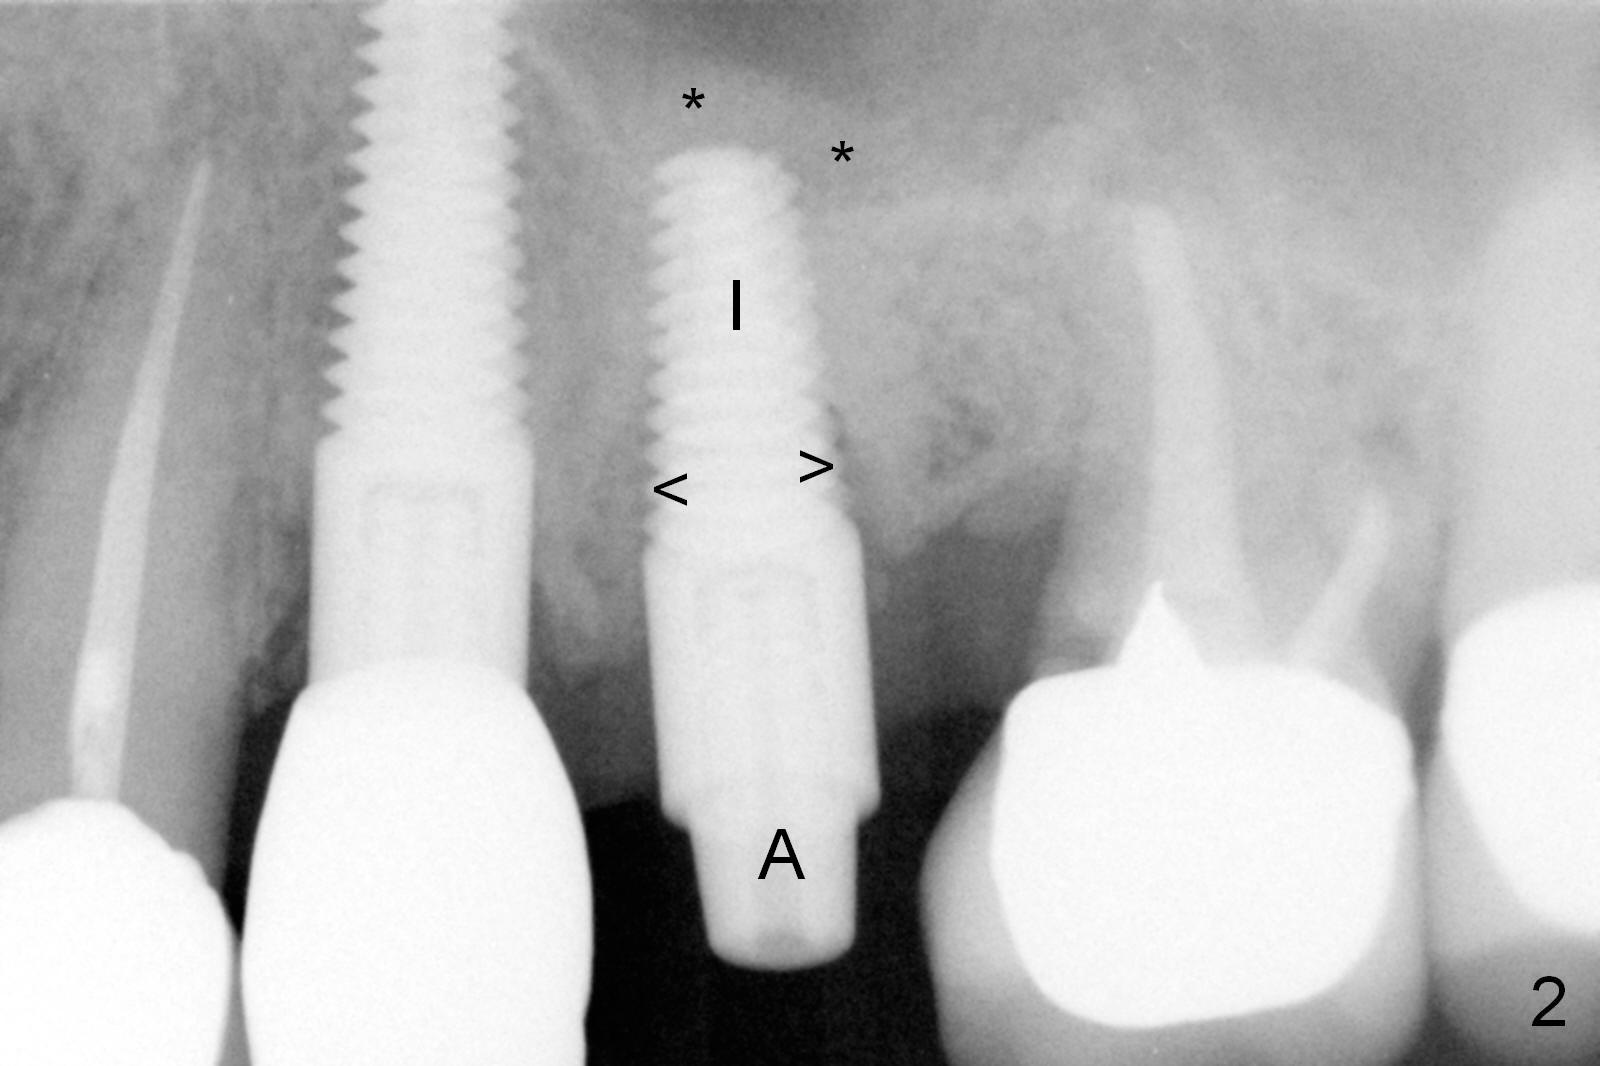

Extraction of the affected 2nd premolar is easy; the apical bone is so hard that drill and reamers have to be used for osteotomy, followed by insertion of a 4.5 mm tap with stability (Fig.1 T). The sinus floor (^) is lifted. There is no sign of sinus membrane perforation before placement of a 4.5x14 mm implant (Fig.2 I); sinus lift is performed (*: autogenous bone mixed with Mineralized Cancellous Human Allograft, Impladent); an immediate abutment (3.5x3 mm) is placed (A). With gauze placed in the buccal gap (Fig.3 G), the margin of the implant (I) is prepared for an immediate provisional fabrication. Mixture of autogenous bone (from reamers), allograft and Osteogen is placed in the remaining socket (Fig.4,5 *). When the relined (1st modification), trimmed and polished provisional is reseated (Fig.6 P), the bone graft (*) is not completely covered. New acrylic (2nd modification) is added to the margin of the provisional (Fig.7 *) for containment of the graft. There is almost no buccal plate; Osteotape (collagen membrane with Osteogen) is placed against the buccal wall of the socket prior to bone grafting. The remaining small pieces of the Osteotape (Fig.7 <) are laid over the bone graft before reseating the final provisional. With "complete socket seal", perio dressing is unnecessary.